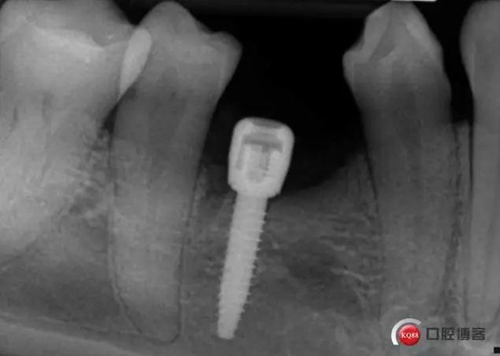

偏遠(yuǎn)中植入。 術(shù)后病人恢復(fù)良好, 無(wú)感覺異常。

三個(gè)月后上基臺(tái)